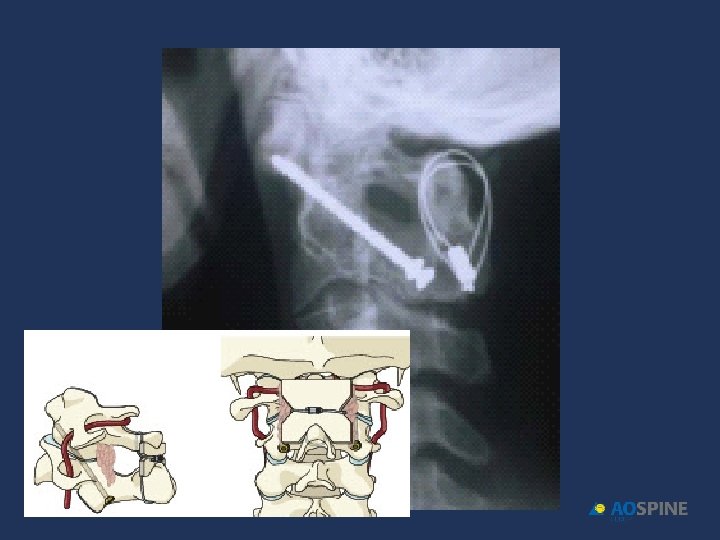

HANGMAN´S FRACTURES surgical treatment C 2 C 3 DISC DISRUPTION INHABILITY TO MANTAIN ALIGNMENT NON UNION POSTERIOR FUSION C 1 C 3 ANTERIOR DISCECTOMY + FUSION C 2 C 3 POSTERIOR C 2 PEDICLE SCREWS

HANGMAN´S FRACTURES INSTABILITY: ANTERIOR DISPLACEMENT C 2 C 3 > 50%

Francis grade V